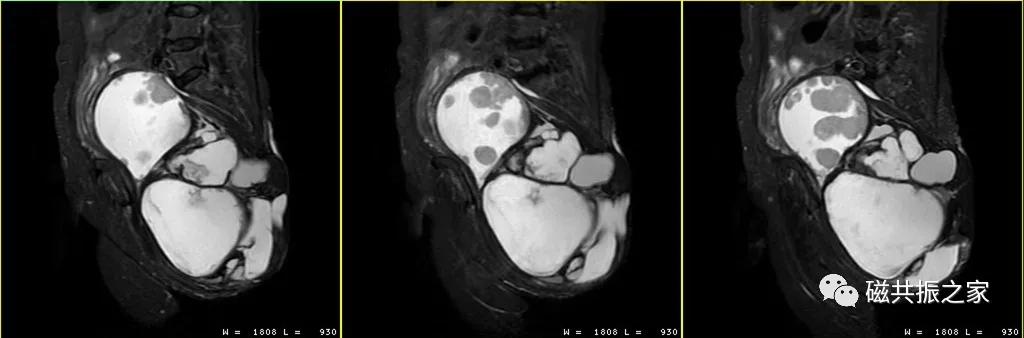

【MRI检查也要选时候 】

一些部位在特殊的时期是不宜做MRI检查的,如月经期间的子宫检查、乳腺检查,前列腺穿刺后前列腺检查等,这些部位如在特殊期间行MRI检查,一些正常性的生理信号可能会被误解读。

【非选择性的STIR序列并不是万精油 】

STIR序列不能用于增强扫描这是大家都知道的,但是你是否知道很多平扫也是不能用SITR序列扫描的。

如果使用FS技术压脂效果不理想时,很多人就会想到STIR序列,觉得STIR不管哪个部位都能行,特别是在做范围比较大解剖部位时,为了提高图像质量会使用非选择性的压脂序列STIR序列扫描。这样做的结果就是很多T1弛豫时间与脂肪组织相近的成分(如陈旧性出血、蛋白含量较高的黏液成分等)也会被抑制为低信号被误解为脂肪信号,造成漏误诊。